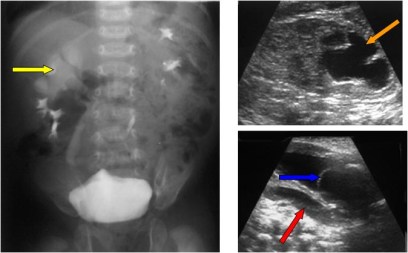

Signo de rotura vesical extraperitoneal en la cistografía. La extravasación del contraste hacia los tejidos blandos extraperitoneales y, especialmente hacia el espacio prevesical de Retzius, da un aspecto característico de «llamaradas» o «resplandor solar“ (flechas verdes).

Obsérvese la fractura de rama ilio-pubiana derecha (flecha azul) y la diástasis de la articulación sacroilíaca izquierda (flecha amarilla).